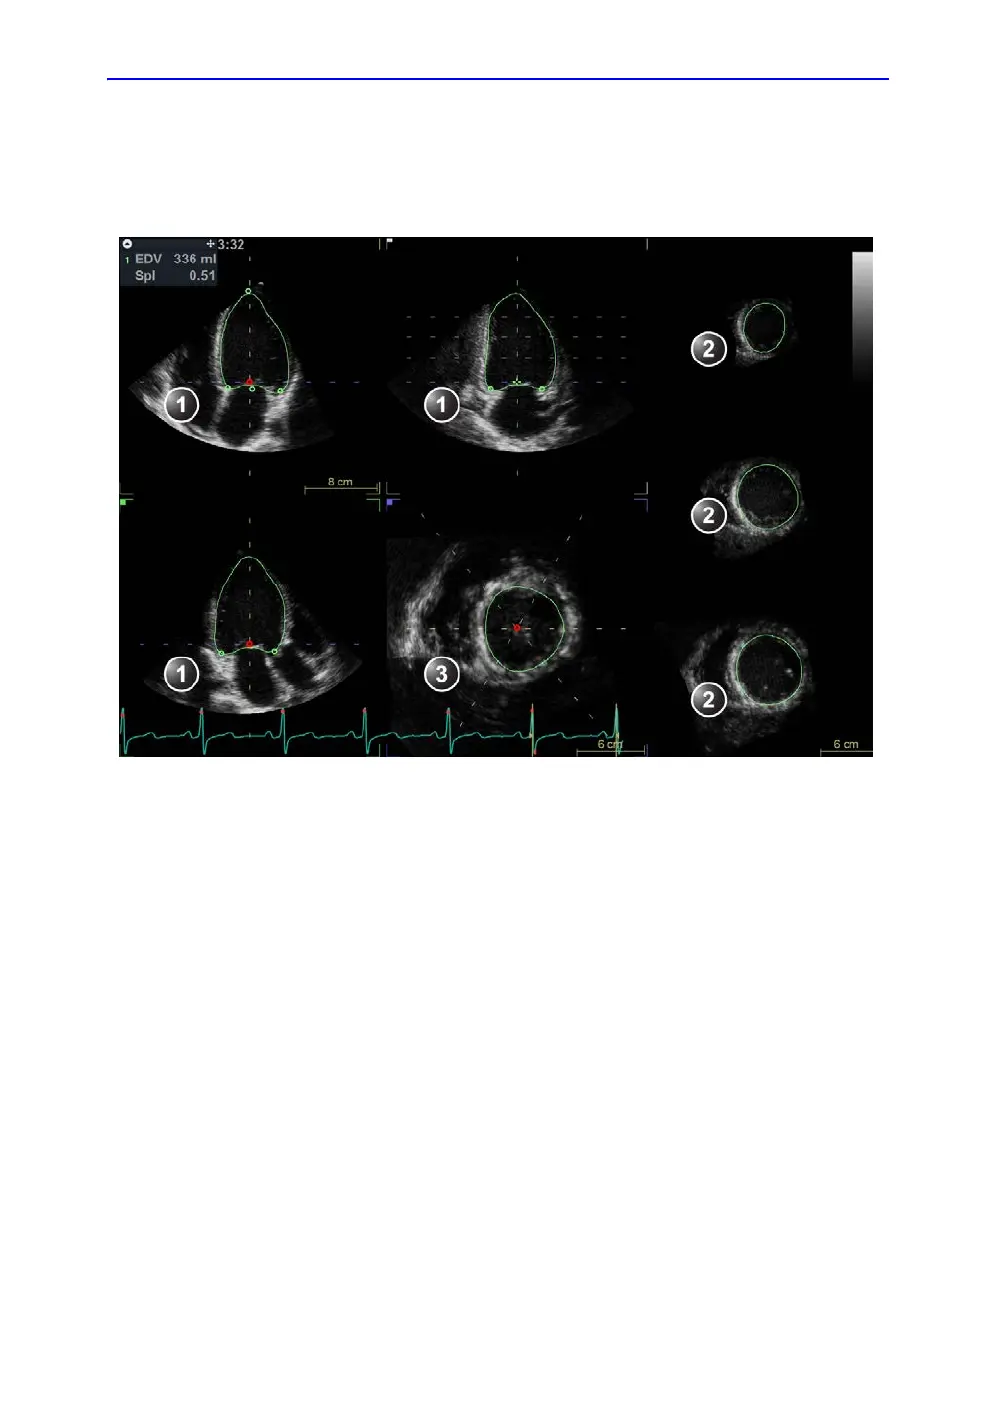

Figure 8-28. Left ventricle contour detection (end-diastole)

1. Apical views

2. Short axis views

3. Interactive view